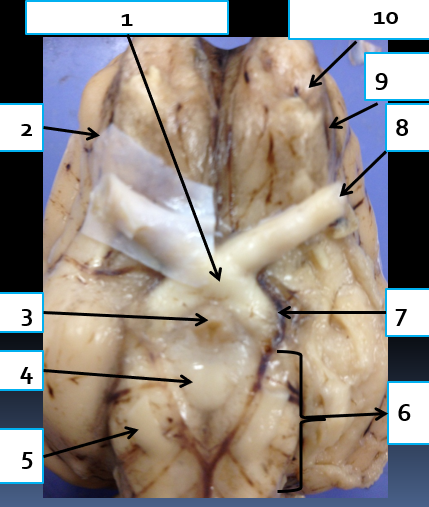

1

cerebrum, complex reasoning

2

septum pellucidum, separates lateral ventricles

3

lateral ventricle, take CSF from choroid plexus to third ventricle

4

optic chiasma, area where medial portions of optic nerves cross

5

thalamus, relay station for sensation except smell

6

hypothalamus, drives (sex, hunger, thirst)

7

mammillary body, relay station for olfaction

8

pons, connects brain with lower CNS centers

9

medulla oblongata, controls vital autonomic functions like heart rate

10

spinal cord, reflex area

11

fourth ventricle, takes CSF from cerebral aqueduct to central canal

12

superior and inferior colliculi of corpora quadrigemina, contains visual and auditory reflex center

13

arbor vitae, conducts impulses concerened with equilibrium

14

cerebral peduncle, connects cerebrum to pons

15

pineal gland, produces melatonin

16

fornix, concerned with olfaction

17

corpus callosum, connects cerebral hemispheres